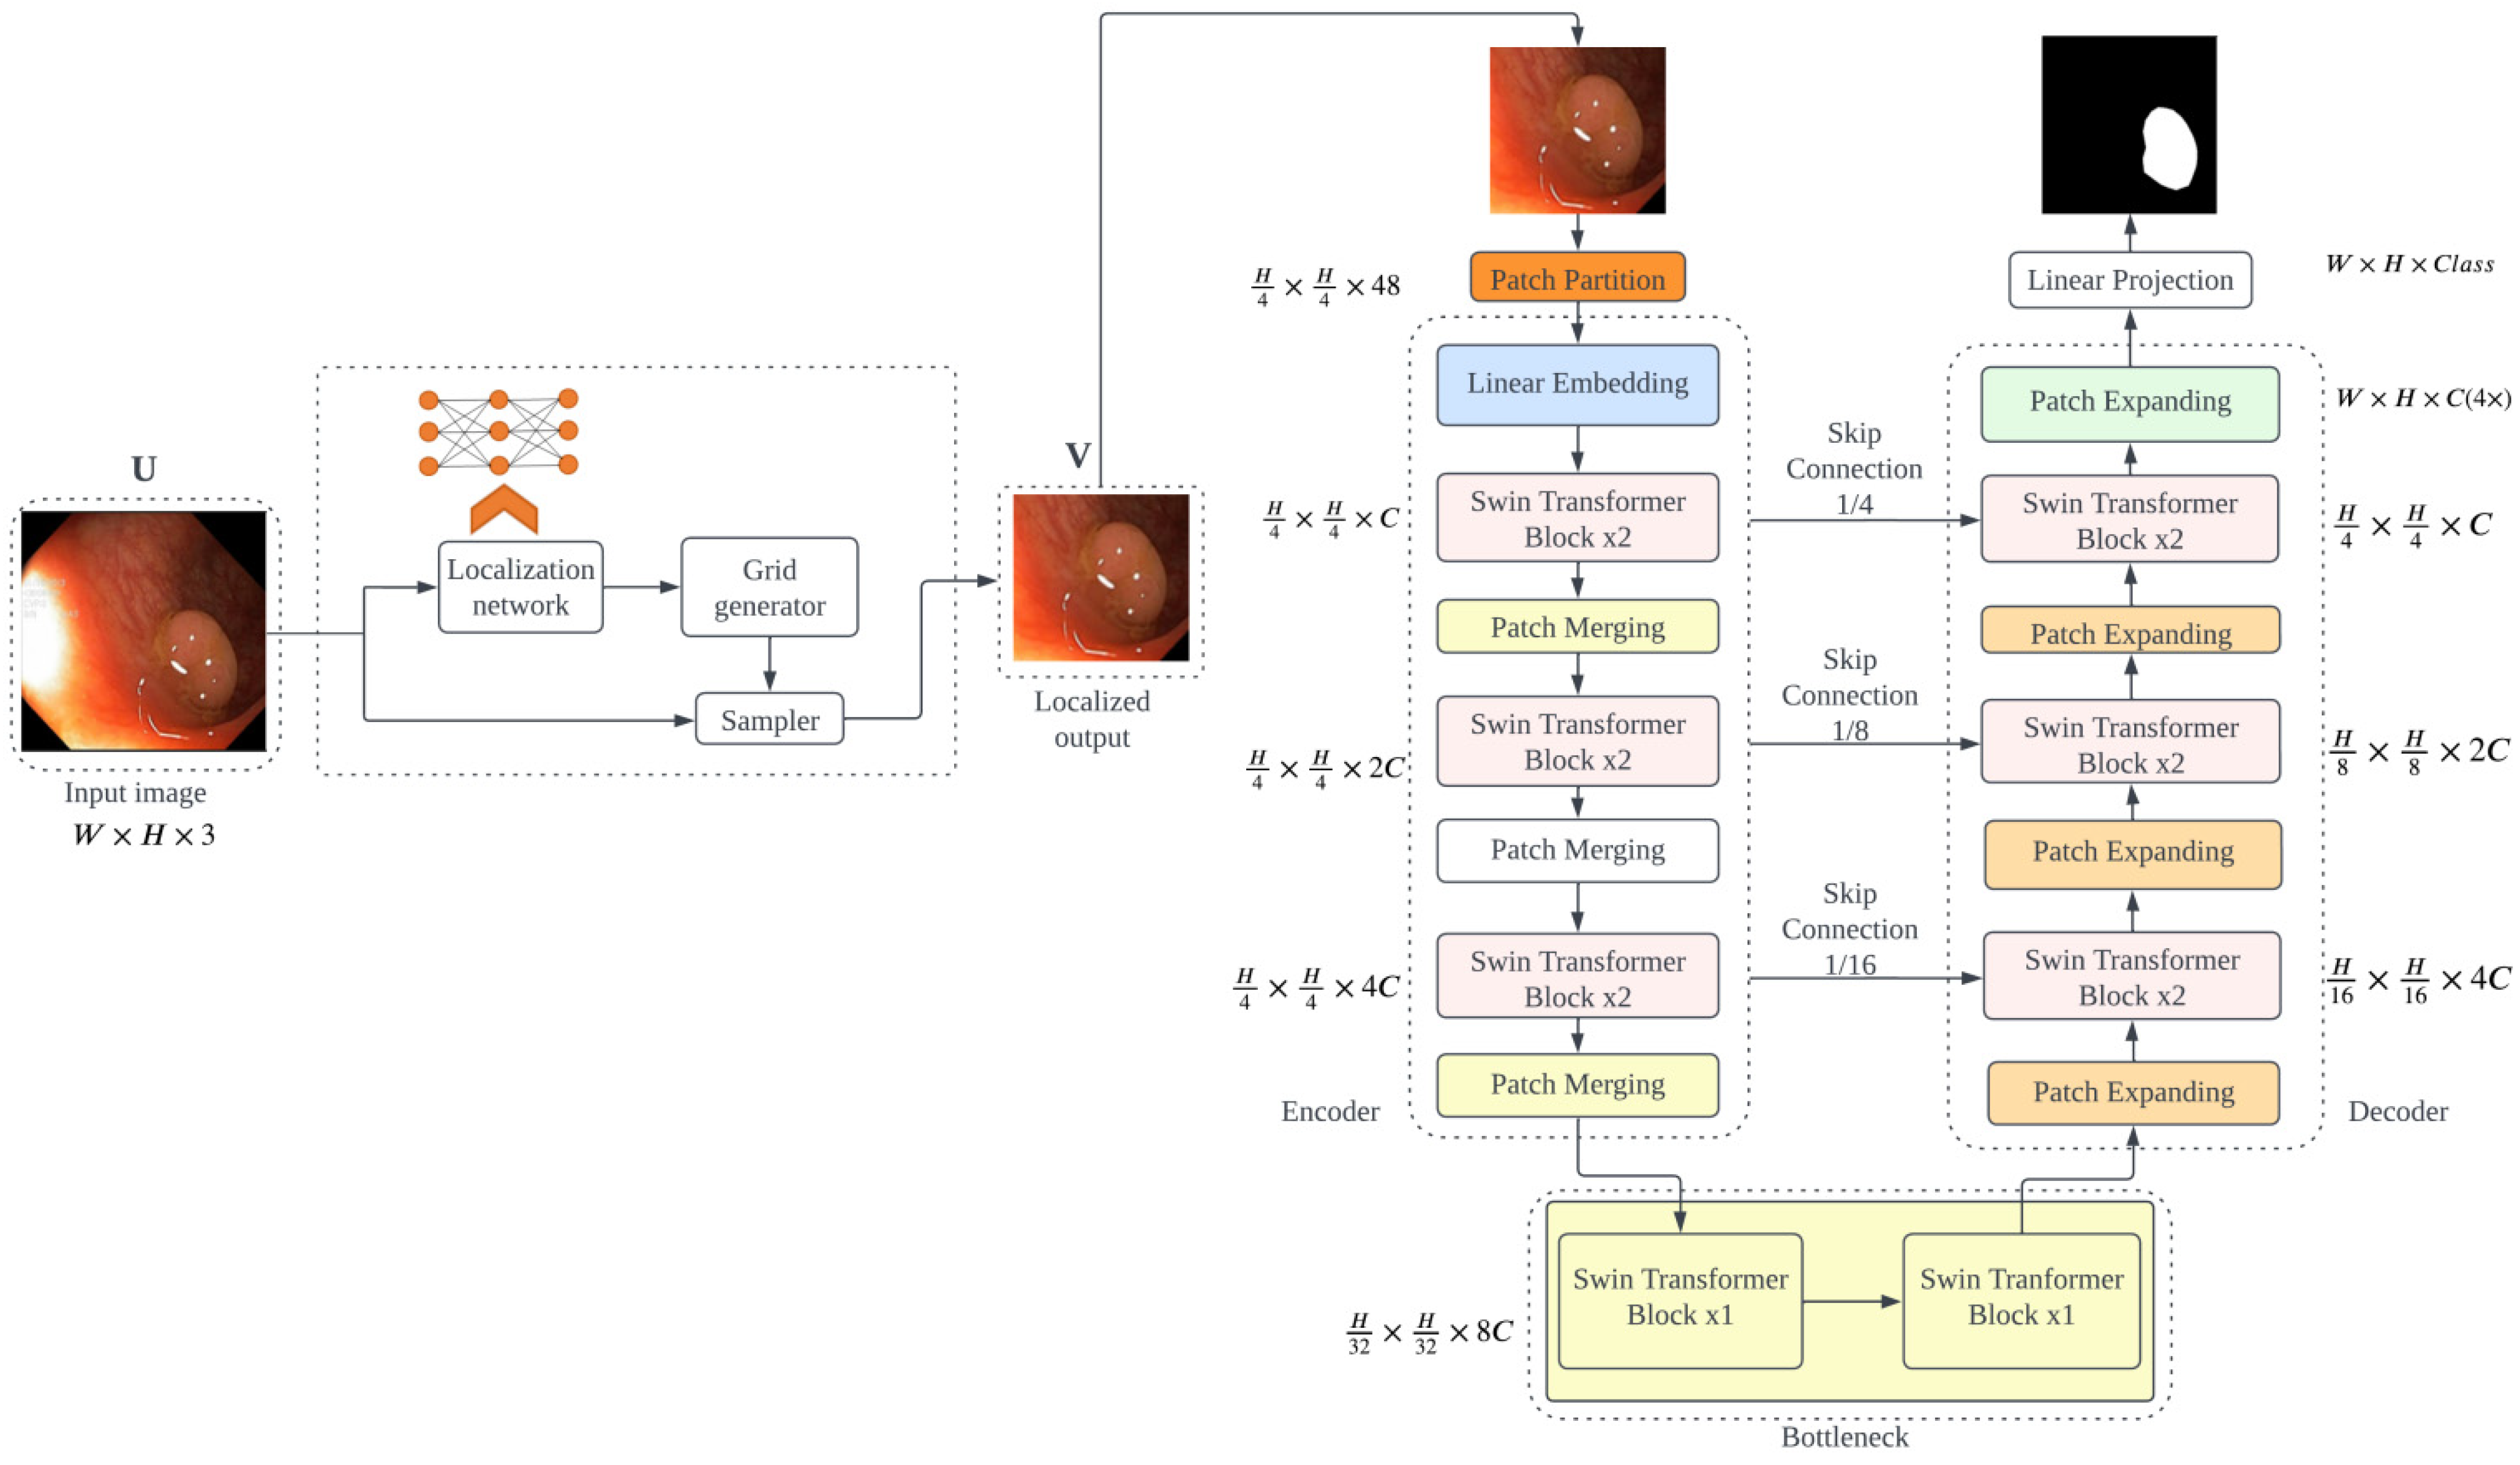

- PUTS: A novel Swin-Unet transformer-based polyp segmentation model;

3.2. PUTS: Vision Transformer-Based Polyp Segmentation

3.2.2. PUTS Architecture

3.2.3. Model Definition

3.2.4. Implementation